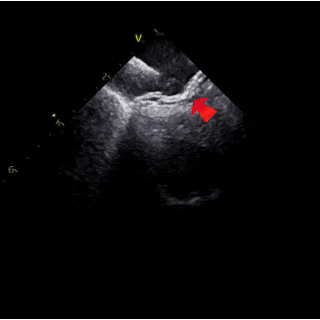

ICE下可见明显长隧道PFO

ICE下测量膨出瘤基底24mm

ICE下清楚显示右盘已展开呈球状,钢缆轻轻前推使其贴靠房间隔

ICE下牵拉试验可见封堵器整体移动

ICE下可见封堵器成型良好,左右盘面牢牢夹持房间隔,且无残余分流,封堵手术成功